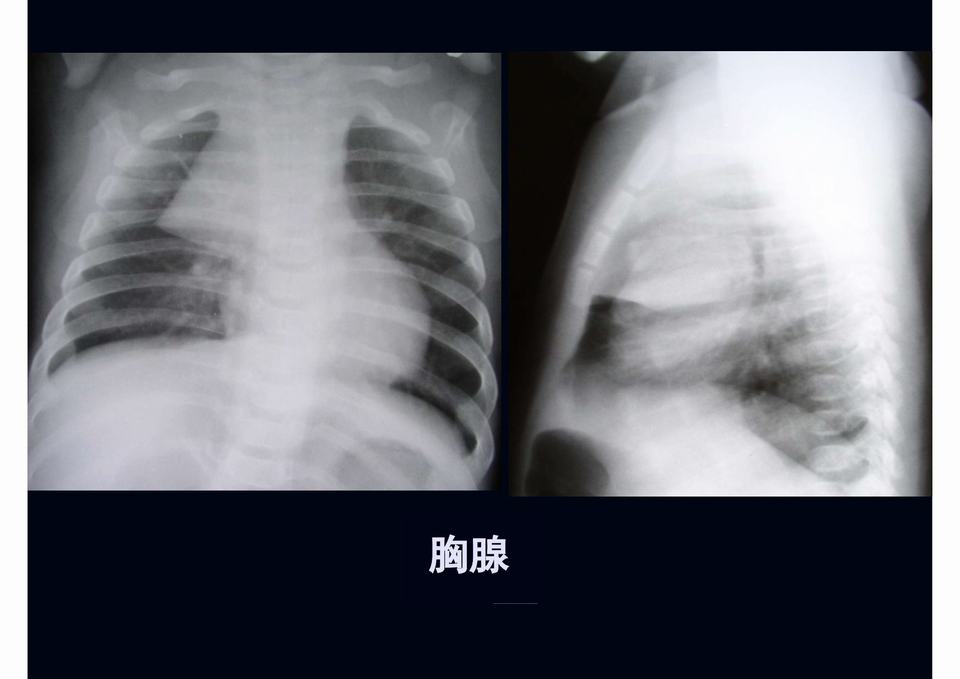

图04